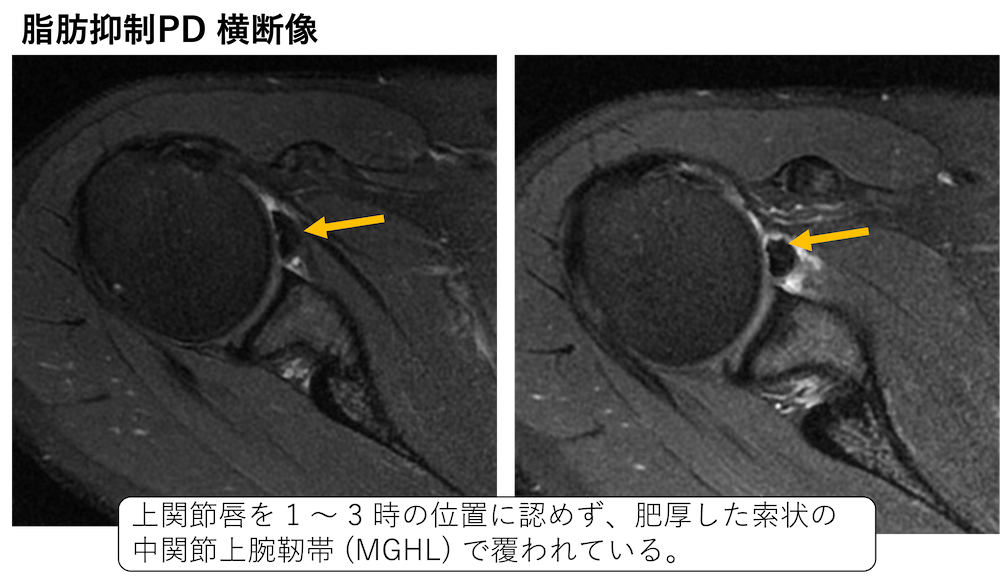

関節唇および肩甲上腕靱帯の正常変異とMRI画像所見のポイント。医療機関の方へ|御池クリニック。SLAP損傷 | ラドライフ。「関節のMRI」上谷 雅孝 / 青木 隆敏 / 神島 保定価: ¥ 13000#上谷雅孝 #上谷_雅孝 #青木隆敏 #青木_隆敏 #神島保 #神島_保 #本 #自然/医療・薬学・健康裁断済みのため全体的に状態が悪いとしております。口腔外科学 第4版 医歯薬出版 裁断済み。。医療機関の方へ|御池クリニック。素人裁断であることをご了承ください。また、本商品の他にも多数医学書を出品しておりますので、合わせてご検討ください。【koro】イラスト解剖学 改訂10版 最新版